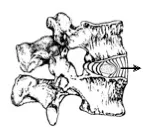

Disc bulges and herniation

When a neck or back is subject to trauma, discs can bulge or herniate into the spinal canal, causing the cord’s nerve roots to be compressed against the bony structures that surround it.

Should the disc press upon the nerve roots that fan out from the spine, it can lead to significant nerve root damage, which can cause shooting pain and loss of sensation.

In severe trauma, the bulging or herniated disc can sometimes compress against the cord’s nerve roots and even the spinal cord itself.

Should part of the spinal cord get compressed, a condition known as myelopathy, it can present a high risk of severe and permanent paralysis of the arms and legs.